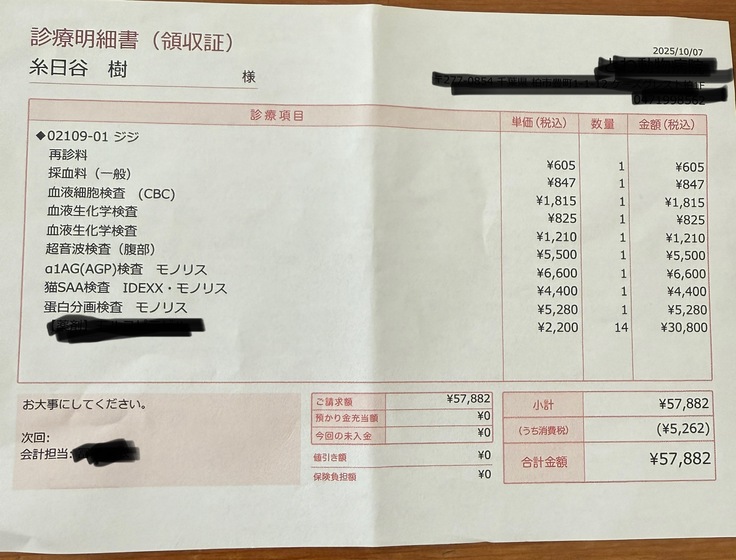

⬇️投薬14日目(10/7)

投薬を始めて2週間、受診日でした。

いつも通り検査、この日は腹水を見るために腹部エコーもしていただきました。

驚くことに結果はとっても良好で、全ての値がほぼ正常値まで戻っていました。

そして腹水もほぼ全てなくなってくれていました。

薬が効いてくれているおかげです。

9/23時点で1.4キロだった体重は1.56キロまで増えてくれていました。

頑張って薬を飲んでくれているおかげで、日に日に元気を取り戻してきています。

現時点までの治療費です⬇️

診察代、検査代、薬代の合計で210.386円

10/7▶️57.882円